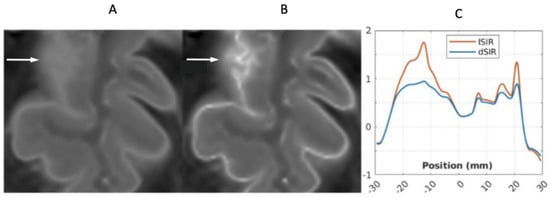

Figure 13 shows a leucocortical lesion in a 41-year-old female patient with MS in remission. The lesion appears blurred and relatively featureless on the narrow mD dSIR image (Figure 13A), but shows a disrupted boundary within the lesion on the lSIR image (Figure 13B). Figure 13C shows dSIR (blue) and lSIR (orange) signal profiles across the lesion. These are plots of signal vs. distance in mms on the image. The lSIR profile has higher signal and generally steeper slopes than the dSIR profile, corresponding to the graphs in Figure 4.

Figure 13.

Forty-one-year-old female patient with MS. A leucocortical lesion is shown in the right medial frontal lobe on the narrow mD dSIR image (A) and the matching synthetic lSIR image (B) (arrows). There are also left to right profiles with signal plotted against position (in mm) for the dSIR (blue) and lSIR (orange) images (C) at the level of the horizontal arrows shown in (A,B). No boundary between white matter and gray matter is seen within the lesion in (A). A disrupted high signal boundary between white matter and gray matter is seen in the lesion in (B). The lSIR profile (orange) has higher signal and generally steeper slopes than the dSIR profile (blue) in (C). The difference in signal (or contrast) achieved for the same change in position is generally greater with the lSIR filter.